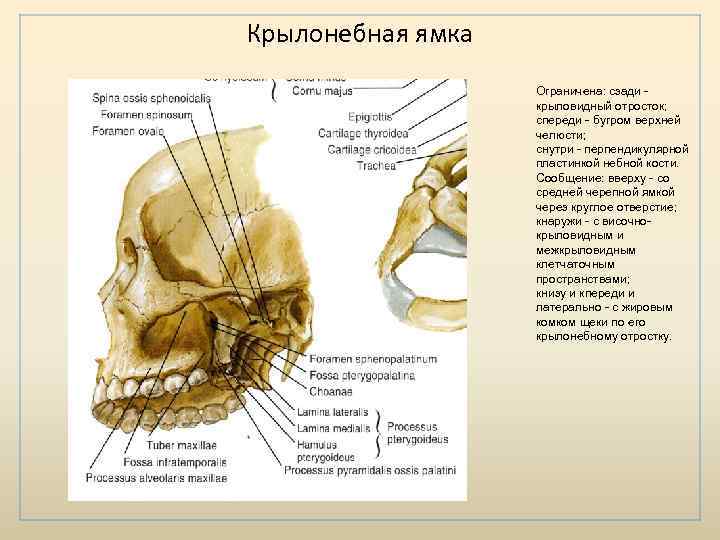

Анатомические особенности: фотографии ямок черепа, височной и подвисочной крылонебной